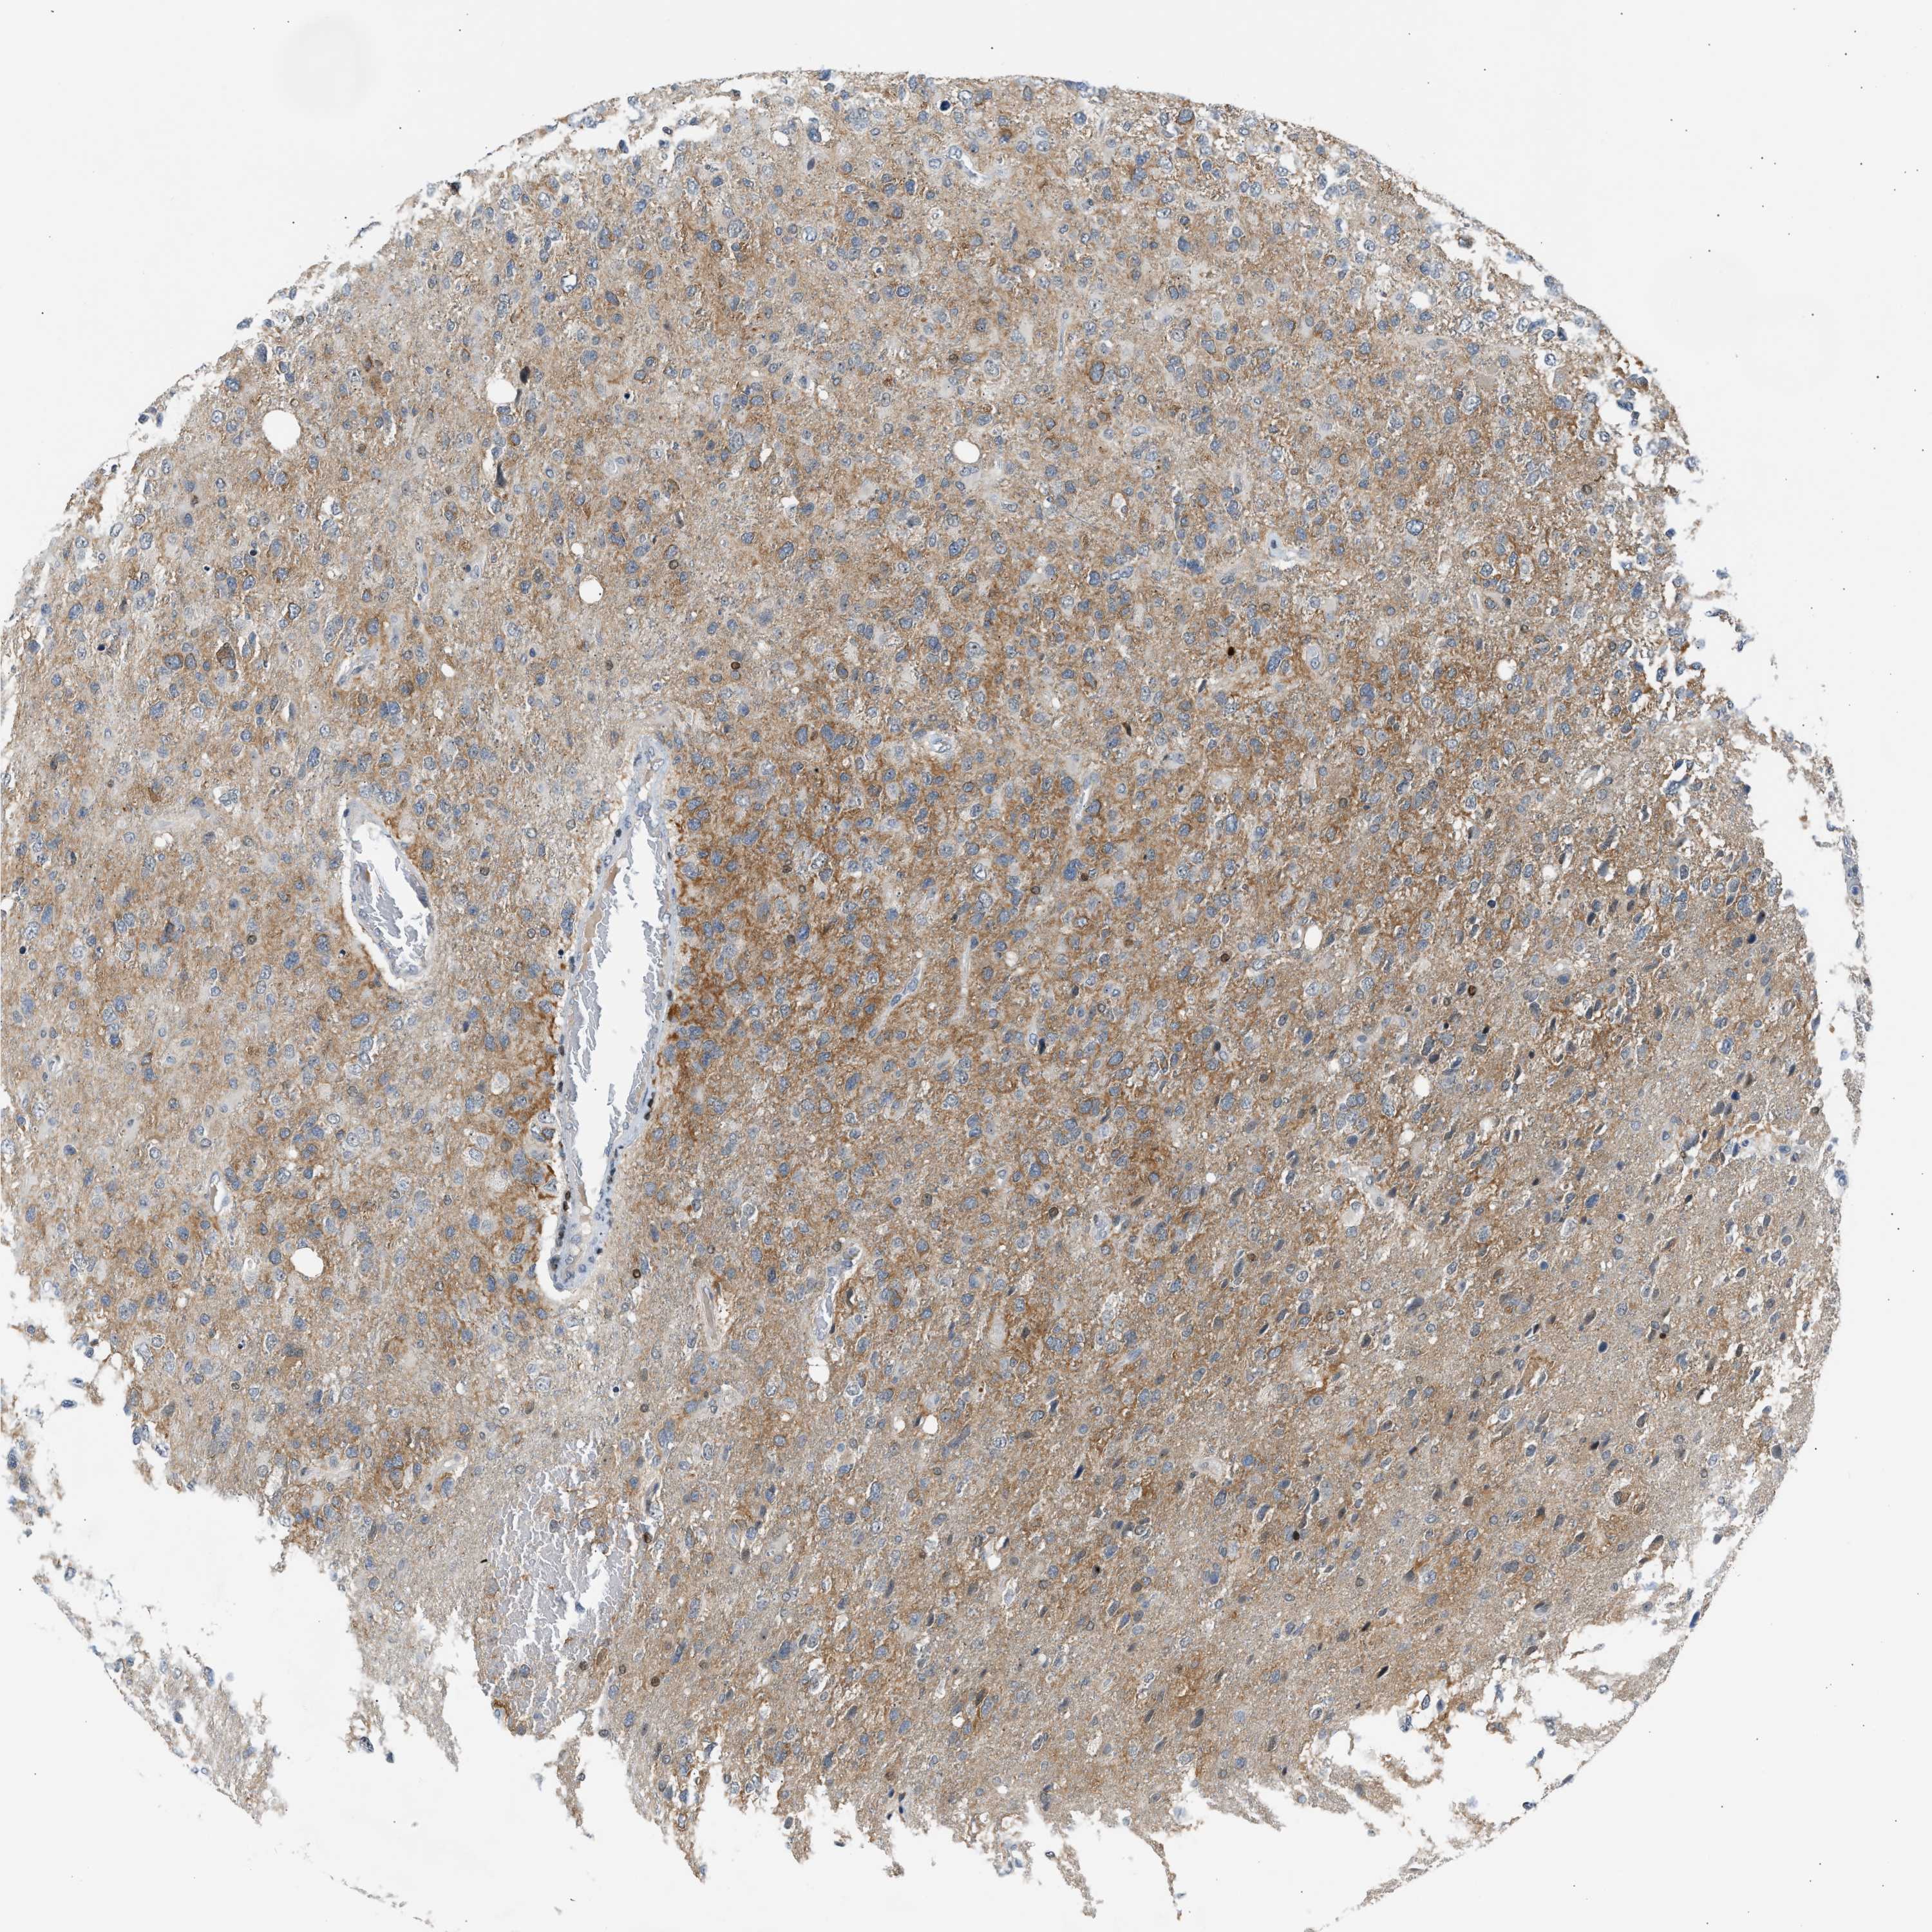

GLIOMA - Protein expressioni

A mouse-over function shows sample information and annotation data. Click on an image to view it in a full screen mode. Samples can be filtered based on level of antibody staining by selecting one or several of the following categories: high, medium, low and not detected. The assay and annotation is described here.

Note that samples used for immunohistochemistry by the Human Protein Atlas do not correspond to samples in the TCGA dataset.

Antibody stainingi

Antibody staining in the annotated cell types in the current human tissue is reported as not detected, low, medium, or high, based on conventional immunohistochemistry profiling in selected tissues. This score is based on the combination of the staining intensity and fraction of stained cells.

Each image is clickable and will lead to virtual microscopy that enables deeper exploration of all samples and also displays staining intensity scores, fraction scores and subcellular localization as well as patient and tissue information for each sample.

Antibody CAB020139

Staining

High

Medium

Low

Not detected

Intensity

Strong

Moderate

Weak

Negative

Quantity

>75%

75%-25%

<25%

None

Location

Nuclear

Cytoplasmic/membranous

Cytoplasmic/membranous,nuclear

Glioma, malignant, High grade

Glioma, malignant, Low grade